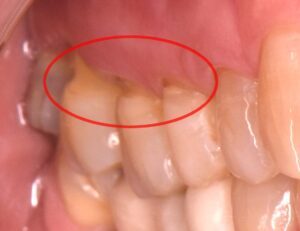

知覚過敏の原因のひとつとして、歯と歯茎の境目付近の歯質が欠けてしまい、神経が近くなることでしみる症状が出ることがあります。この状態が、昔から「くさび状欠損」と呼ばれてきたものです。

NCCLは「虫歯ではなく、歯の一部が失われてしまう状態」の一種で、特に歯のくびれた部分に生じるものと定義されています。最近では「Tooth Wear(歯の摩耗・損耗)」という言葉もよく使われるようになっています。